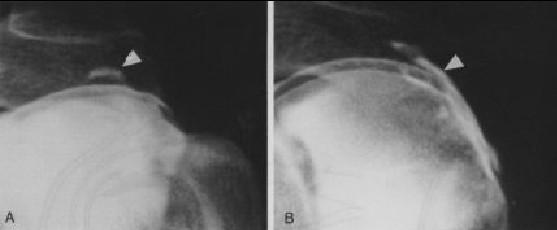

Artrografía…

Indicaciones de la Artrografía • Ruptura del Maguito de los Rotadores • Capsulitis Adhesiva • Alteraciones del Tendón del Bíceps • Luxaciones Crónicas • Evaluación de Inflamación Sinovial • Hombro Congelado

Artrografía